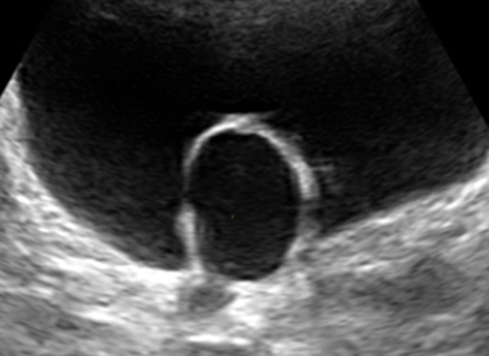

输尿管囊肿声像图:从静态声像图可见,囊性肿块嵌入在膀胱腔内,运用嵌入器官征思维方法,提示该囊性肿块来源于膀胱之外